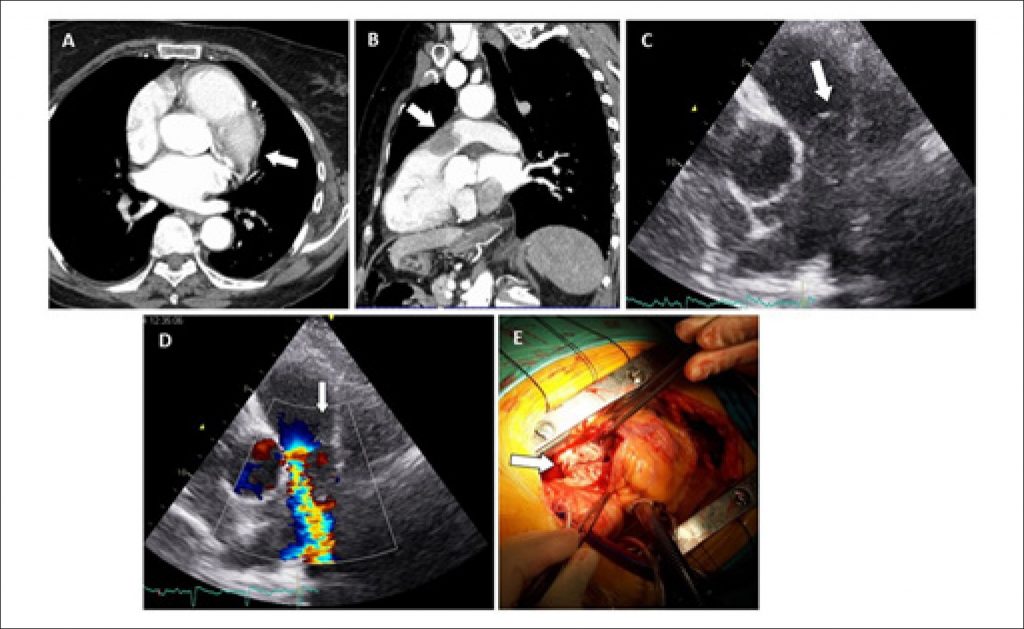

A 79-year-old female with no relevant past medical history was admitted in our emergency department for dyspnea on minimal exertion and chest discomfort over 2 weeks. Blood gas analysis showed severe hypoxemia and hypocapnia. Troponin was slightly positive. Despite a negative D-dimer assay, contrast-enhanced chest CT was performed to exclude pulmonary embolism. It showed a large filling defect centered in the pulmonary valve plane (Panels A and B). Bedside transthoracic echocardiogram showed a large echodense mass, apparently mobile, extending across the right ventricle outflow tract, pulmonary valve, and the main pulmonary artery, with dilatation of the right sided chambers and transtricuspid peak gradient of 70 mmHg (Panels C and D). Lower-limb venous compression ultrasound was negative for deep vein thrombosis. The patient remained stable, but required high oxygen inspiration fraction to maintain saturation above 90%. As pulmonary embolism was deemed unlikely given the clinical findings, the patient underwent cardiac surgery. Surgery revealed a pearly mass in the main pulmonary artery obliterating almost the entire lumen and with upstream extension to the pulmonary valve and right ventricle outflow tract (Panel E). The tumor was excised as much as possible and the pulmonary valve was replaced by a homograft. Pathological examination was compatible with angiosarcoma.

Pulmonary artery angiosarcoma is exceedingly rare and carries a very poor prognosis. It can be clinical and radiologically indistinguishable from acute or chronic pulmonary artery thromboembolism. Our clinical suspicion was heightened by a negative D-dimer assay and venous ultrasound and the apparent infiltration of pulmonary arterial walls on CT.